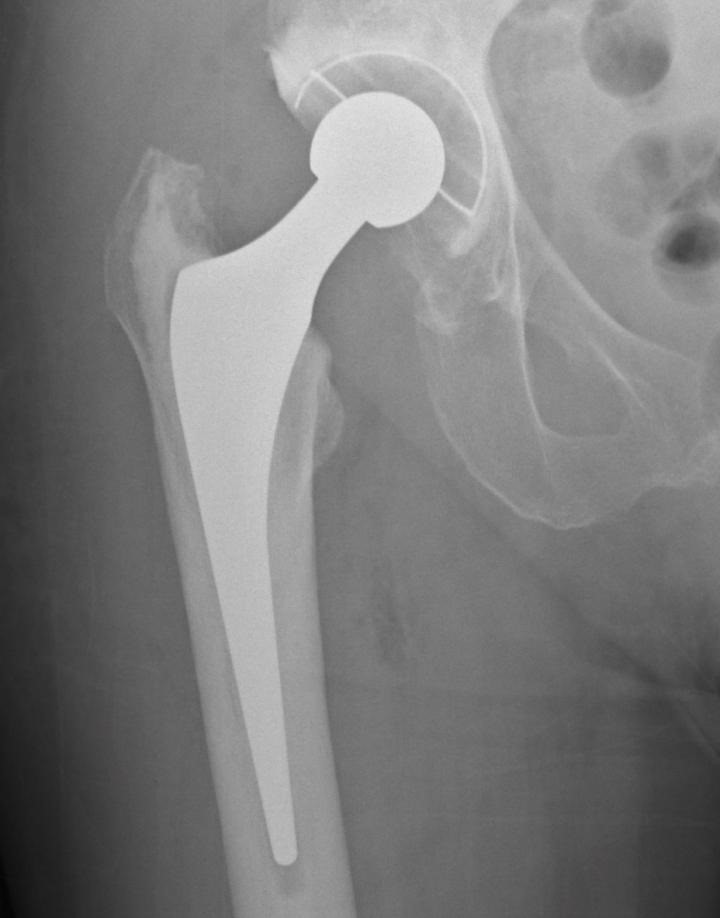

Radiografía de reemplazo de cadera

La cadera afecta especialmente a las personas mayores/ Foto de archivo EP